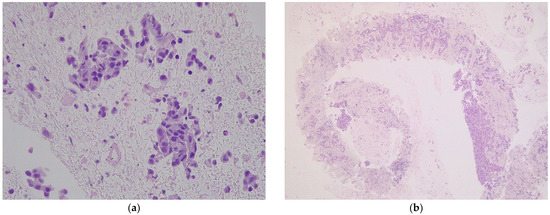

4. Discussion